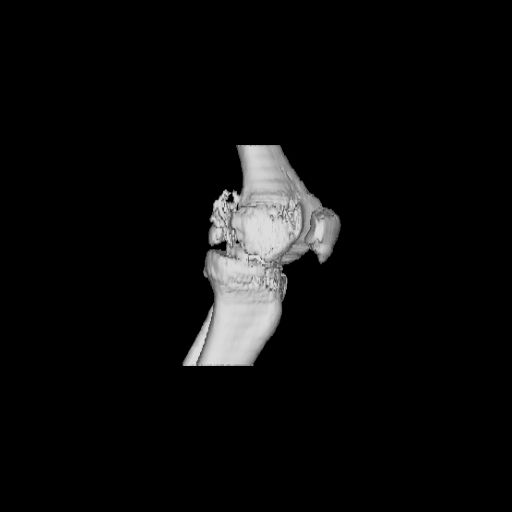

CT shows major bony fragments which are markedly rotated .With this amount of bony damage,you probably should attempt to get reasonably loooking knee with ORIF and thn if he needs a TKR due to pain a few years from now, then tleast you have something looking like a knee that you can replace rather than having to use revision knee for a primary TKR now. 4 weeks is not too long .what is the condition of soft tissues?

При внутрисуcтавных переломах трехмерные (3D) изображения, кроме красивого снимка, не дают полную информацию о состоянии отломков, самыми информативными являются корональные срезы на КТ и обычная длинная ренгенограмма конечности для сравнения оси конечности.

Фронтальные внутрисуставные переломы мыщельков бедра, так называемые Hoffa fracture, не частые, но встречающиеся переломы, в основном они связаны с травмой высокой энергией.

В вашем случае доступ будет медиальный, сопоставить развернутый медиальный мыщелок и фиксацию надо произвести в передне-заднем

направлении шурупами 4.5 мм в диаметре, углубив головку шурупов под хрящ, а поперечную фиксацию - межмыщелковыми шурупами. Желательно применить шурупы 6.3 мм в диаметре. Дополнительная Buttress technique пластина предотвратит перелом от скольжения.